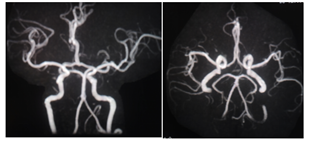

上图所示MRA可见脑动脉未见明显异常,未见狭窄与斑块。DWI所见:双侧小脑半球、胼胝体压部、双侧额顶枕叶多发急性、亚急性梗死。结合临床病史,考虑特鲁索综合征。